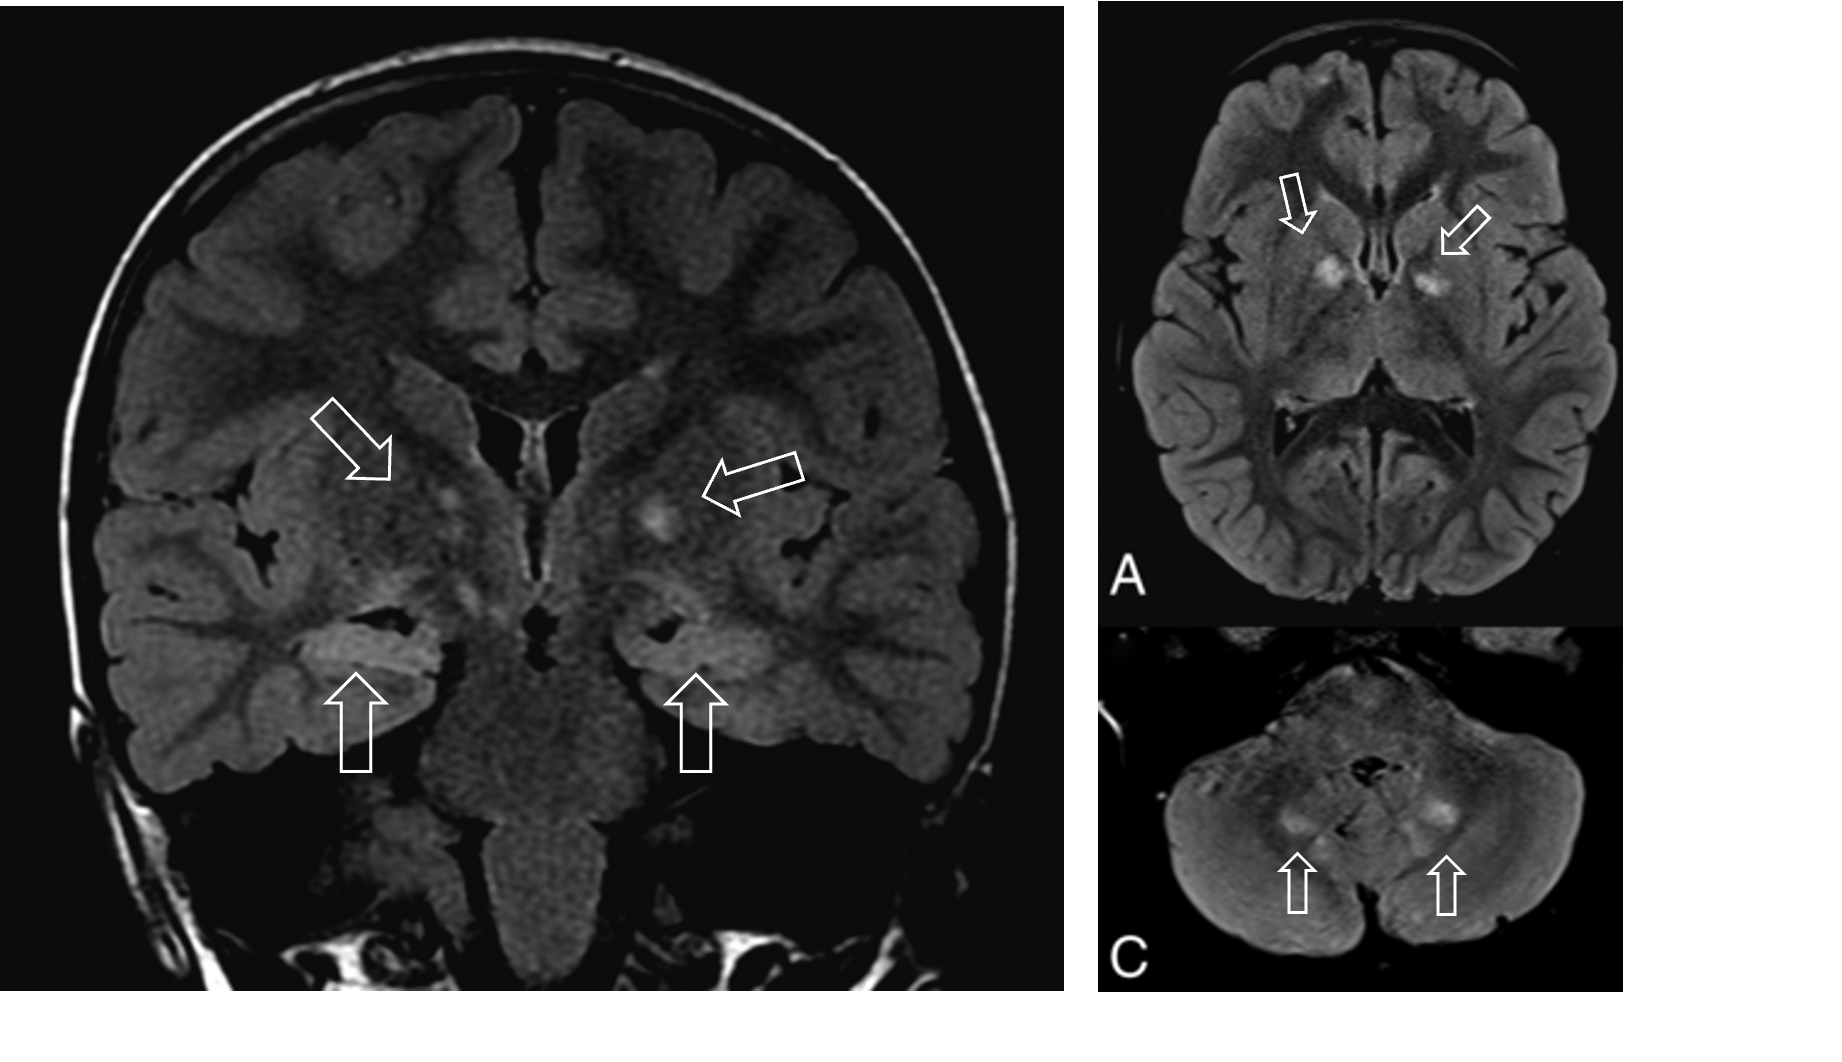

• 뇌 MRI: 시각로, 뇌간, GP, thalamus, IC, 소뇌 등에 T2WI 신호 증강 병변

• cortical dysplasia: cortical tuber, cortical white matter migration line

• subependymal nodule: 측뇌실로 돌출되어 촛농모양으로 관찰,석회화 가능

• subependymal giant cell astrocytoma (SEGA)